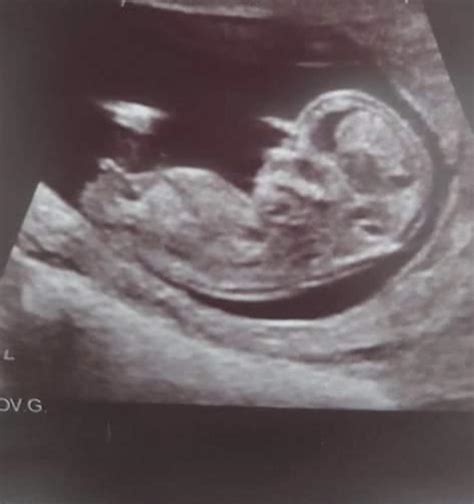

Pregnancy is an exciting journey filled with milestones, and one of the most anticipated moments is the 12 week sonogram. This ultrasound scan, typically performed between 11 and 13 weeks of pregnancy, offers a wealth of information about the developing fetus and the mother's health. Understanding what to expect during a 12 week sonogram can help alleviate anxiety and prepare expectant parents for this crucial check-up.

• Visualizing the Baby: At 12 weeks, the baby is about the size of a plum and has distinct features, including a head, body, and limbs. The ultrasound will show the baby’s movements, such as sucking its thumb or curling its toes.

• Heartbeat Detection: The baby’s heartbeat is usually visible and audible during the scan. The heartbeat rate at this stage is typically between 120 and 160 beats per minute.

The 12 week sonogram is a pivotal moment in the pregnancy journey, offering a wealth of information about the baby’s development and the mother’s health. By understanding what to expect during this scan, preparing adequately, and seeking emotional support, expectant parents can navigate this milestone with confidence and peace of mind. The insights gained from the 12 week sonogram provide a foundation for ongoing prenatal care, ensuring the best possible outcomes for both the mother and the baby.